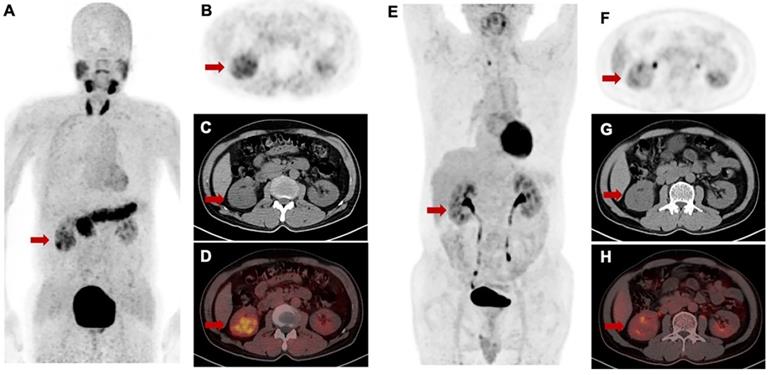

Figure 8

Intra-individual comparison of [68Ga]Ga-FAPI-RGD (A-D) and 2-[18F]FDG (E-H) in a patient with renal cell carcinoma. [68Ga]Ga-FAPI-RGD showed intense uptake in the primary lesion (SUVmax = 5.1), while there was only slight uptake on 2-[18F]FDG PET/CT (SUVmax = 2.7).

For [68Ga]Ga-FAPI-RGD PET/CT, only PET/CT datasets acquired approximately 1 h after injection were used for analysis. No significant difference in mean SUVmax of [68Ga]Ga-FAPI-RGD and 2-[18F]FDG was present in primary tumors (8.9 ± 3.2 vs. 10.3 ± 6.9; p = 0.459). However, marked differences in tumors uptakes between [68Ga]Ga-FAPI-RGD and 2-[18F]FDG were observed in the patient with renal carcinoma. The tumor lesions with low uptake on 2-[18F]FDG PET but high uptake on [68Ga]Ga-FAPI-RGD scan is shown in Figure 8. Among the six patients, three patients had metastatic foci. The number and SUVmax of metastasis were not significantly different between [68Ga]Ga-FAPI-RGD and 2-[18F]FDG (n = 70 vs. n = 69, p = 0.986; for SUVmax, 6.5 ± 2.6 vs. 7.6 ± 5.3, p = 0.373).